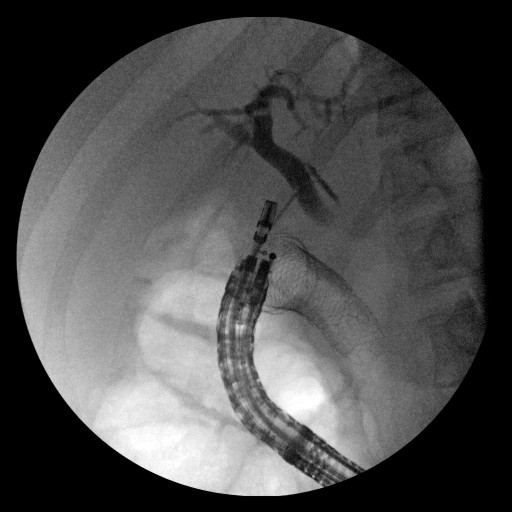

Thus, EUS-guided transduodenal biliary drainage (EUSBD) was performed. A linear array echoendoscope (GF-UCT140, Olympus America, Center Valley, PA, USA) was placed in the duodenal bulb allowing visualization of a dilated common bile duct (Figure 1). A 19-gauge FNA needle (Wilson-Cook Endoscopy, Winston-Salem, NC, USA) was used to perform a transduodenal puncture of the common bile duct through the proximal end of the duodenal stent. Bile was aspirated and a cholangiogram demonstrated good filling of the right and left duct systems with no evidence of a stricture proximal to the puncture site (Figure 2). Under fluoroscopy, a 0.035-inch straight guidewire (Jagwire, Boston Scientific Corporation, Natick, MA, USA) was passed into the biliary tree and directed toward the hilum. The FNA needle was exchanged for a biliary dilating balloon (Hurricane RX, Boston Scientific Corporation, Natick, MA, USA). The choledochoduodenostomy tract was dilated to 6 mm. A 10x60 mm fully covered self-expanding metal biliary stent (Wallfex®, Boston Scientific Corporation, Natick, MA, USA) was placed over the guidewire and deployed under fluoroscopy. One cm of the stent was left protruding into the duodenal bulb through the mesh at the proximal end of the duodenal stent (Figure 3). Good bile and contrast efflux was seen. The final fluoroscopic image did not demonstrate a bile leak (Figure 4). Post-procedure CT imaging demonstrated good positioning of the biliary stent and no evidence of a bile leak (Figure 5).

Figure 2. Cholangiogram obtained through 19-gauge FNA needle in distal common bile duct. |